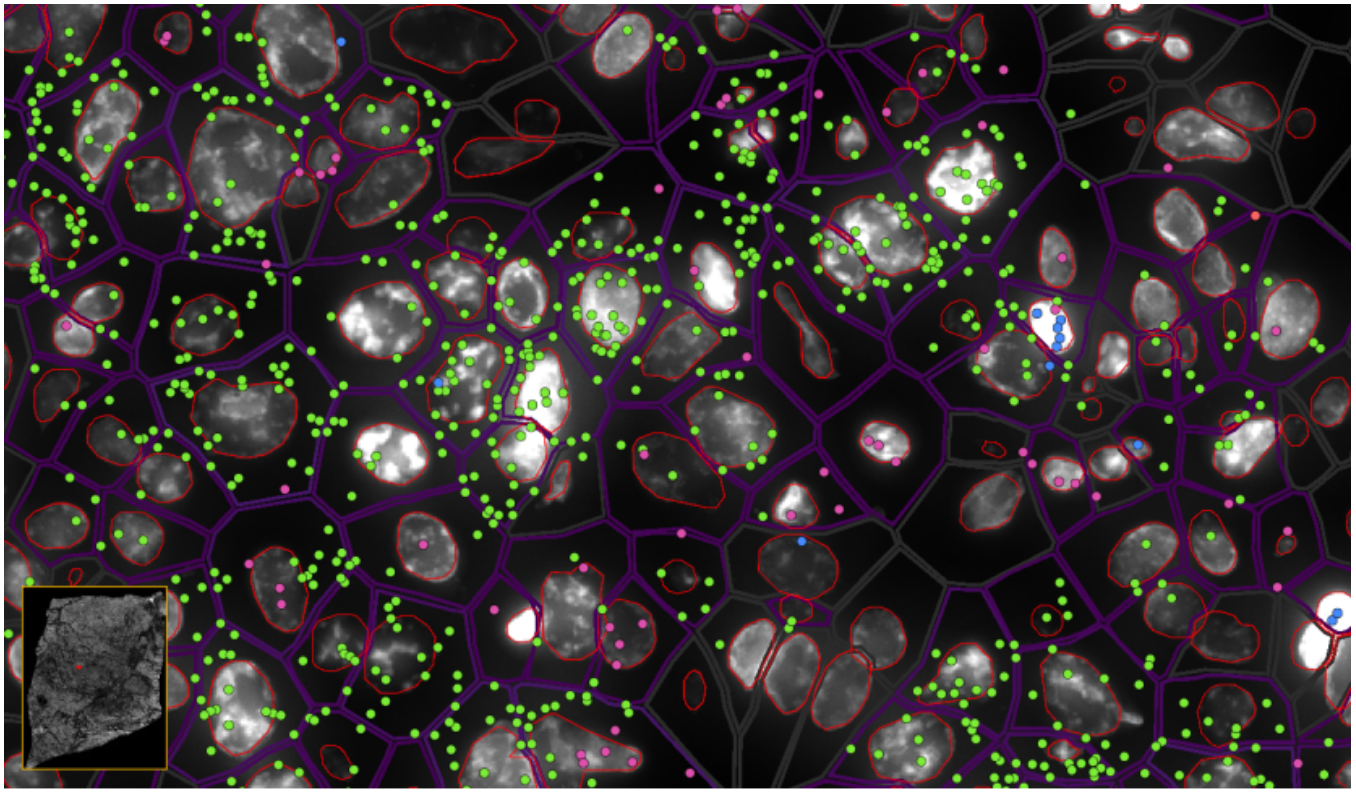

image.png

ͼ5£º½«×ªÂ¼ÌìÖ°Åä¸øÏ¸°û

ͼ6-1£ºÊµÏÖµ¥Ï¸°û/ÑÇϸ°ûÇø·ÖÂʵĿռäת¼×éÆÊÎö£¬£¬£¬£¬£¬Â̵ã-EPCAM , À¶µã-KLRD1 £¬£¬£¬£¬£¬·Ûºìµã-LILRB2